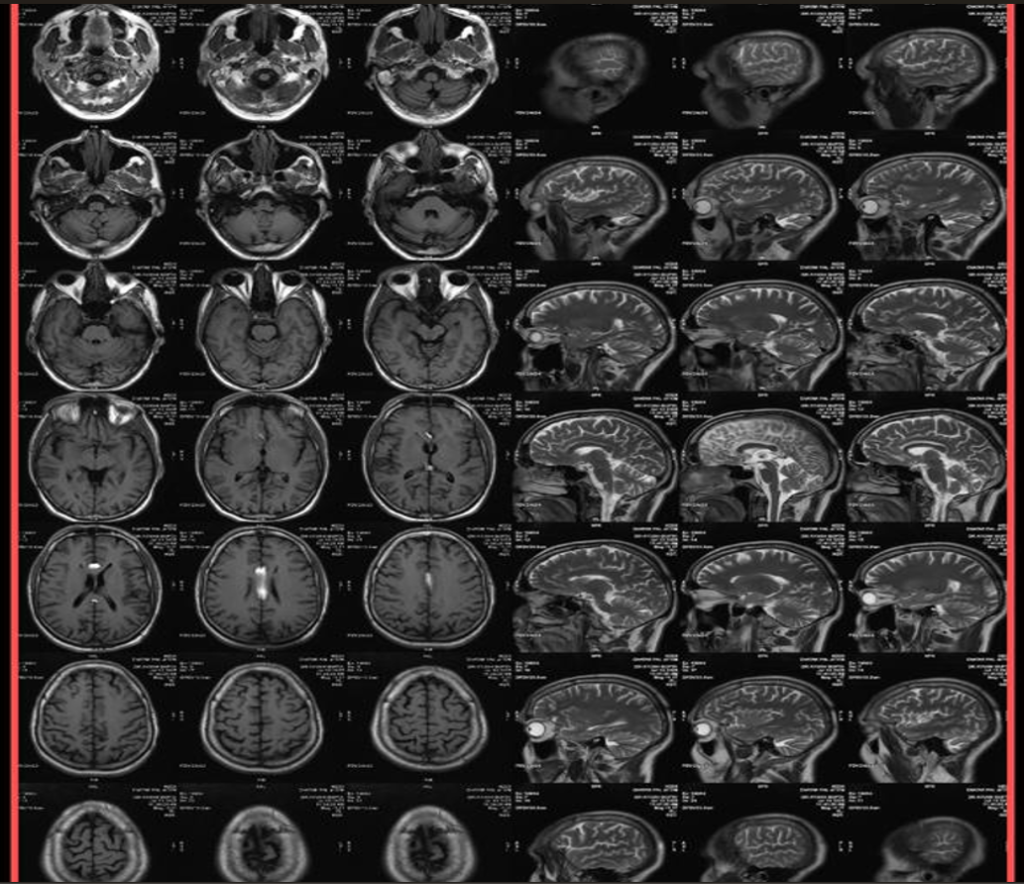

Multiple Sclerosis

The MRI brain scan displays characteristic lesions of multiple sclerosis, showing ovoid hyperintensities in the periventricular regions. These findings, often described as Dawson’s fingers, are critical for diagnosing demyelinating diseases and understanding their progression.

Glioblastoma Multiforme

This MRI demonstrates a large, irregular ring-enhancing lesion with a central necrotic area, indicative of glioblastoma multiforme. Surrounding edema can also be noted. Recognizing these imaging features is essential for differential diagnosis and treatment planning.

Pituitary Macroadenoma

The MRI scan reveals a large pituitary macroadenoma causing compression of the optic chiasm. The sellar mass appears hyperintense on T1-weighted images post-contrast. Understanding these findings is important for evaluating pituitary disorders and planning surgical intervention.

Kernohan’s Notch Phenomenon (MRI Brain)

This MRI demonstrates midbrain compression due to an expanding mass, resulting in contralateral displacement of the cerebral peduncle and indentation on the midbrain. Recognizing this phenomenon is essential for understanding the secondary effects of brain tumors and hematomas.

Thalamic Glioma (MRI Brain)

This MRI scan reveals a thalamic glioma presenting as an infiltrative mass with edema. The rare location and clinical implications of thalamic tumors make recognition and accurate diagnosis essential for treatment planning.